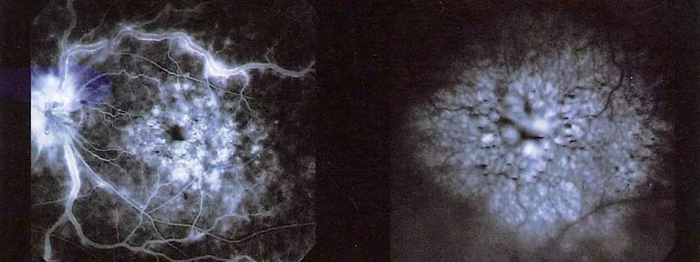

图4:荧光造影检查:黄斑区域有围绕中心区的花瓣样渗漏

图5:接受眼内注射药物治疗后黄斑水肿消退、视力改善

林顺潮指出,局部激光治疗、玻璃体内注射药物或复合治疗,都是糖尿病视网膜病变的主要治疗方式。如能早期发现并进行针对性治疗,病人的视力大多数可以保留。然而如果耽误病情,导致视网膜脱落时间过长,无法得到足够的血液供应,感光神经细胞将可能出现不可逆转的损伤。即使将视网膜复位,但病人手术后视力恢复的时间会较长,甚至可能无法恢复。

林顺潮表示,在深圳希玛林顺潮眼科医院,他接诊最多的就是疑难眼病,其中不乏因糖尿病引发的视网膜病变、视力减退。曾经广受全国关注的“中国最美爸爸”王万林,也是因为身患糖尿病多年,引起眼睛视网膜病变、黄斑水肿以及黄斑出血等多种病变合并难题,几乎濒临失明的边缘。2015年3月,希玛眼科医院向他伸出援手,以林顺潮教授为首、刘姝博士及海内外专家组成的医疗团队为他量身定制了综合手术治疗方案。经过激光治疗配合玻璃体注药后,现在他的视力已明显提升到1.0。